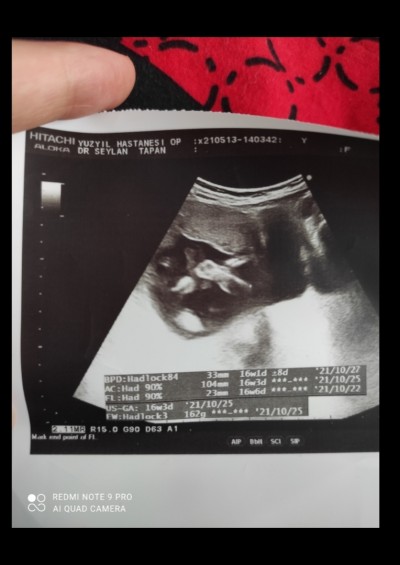

böyle çıkıntı olunca erkekmi oluyor

Bebeğin kafasını ayaklarını ayırt edemedim:D